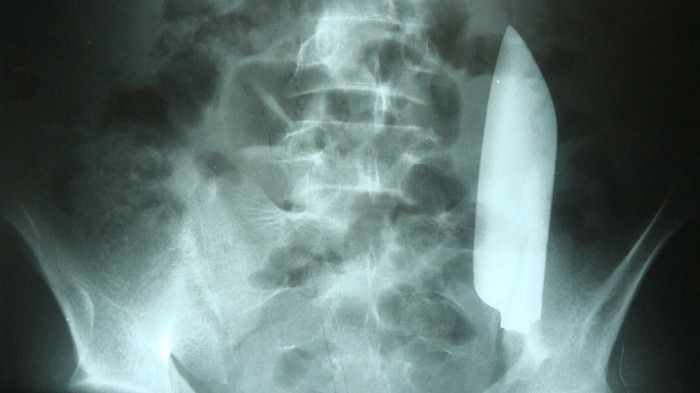

Ketika diperiksa, pria 22 tahun itu mengaku tak mengalami gejala lain selain sakit perut. Namun sang dokter langsung meminta tindakan rontgen. Akan tetapi betapa terkejutnya ia saat menemukan sebuah pisau yang bersarang di perutnya.

Pisau tersebut tampak melintas dari bagian kanan ke kiri perutnya. Dari laporan kasus jurnal Cureus, pisau yang ada di tubuh pria itu sama sekali tidak melukai organ dalam lain.

Foto pria di Nepal perutnya kemasukan pisau (via cureus journal)